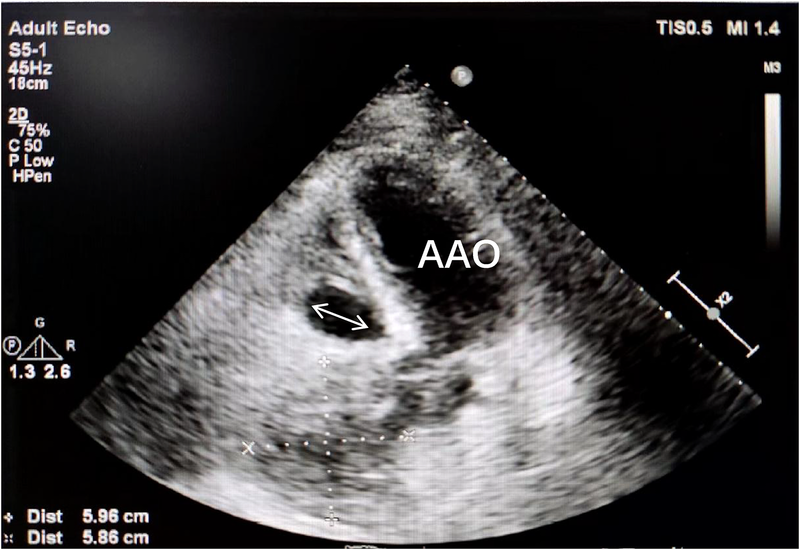

Transthoracic echocardiography (Figure 1) revealed a tumor-like abnormal hypoechoic area measuring approximately 70 mm × 66 mm × 75 mm located about 1 cm from the aortic valve annulus, extending outward from the sinus. This mass communicated with the aorta through a 15 mm × 9 mm defect, with blood flow directed from the aorta to the right coronary artery. Contrast-enhanced computed tomography angiography (Figure 2) confirmed a spherical dilatation (6.0 cm × 7.5 cm) in the right anterior aspect of the ascending aorta. A defect measuring approximately 1.1 cm in diameter was seen in the anterior aspect of the ascending aorta, connecting with the spherical dilation. Compression was noted on the ascending aorta root, aortic sinuses, and right atrium.

Figure 1. A tumor-like abnormal hypoechoic area (white arrow) measuring approximately 70 mm × 66 mm × 75 mm located about 1 cm from the aortic valve annulus, extending outward from the sinus. RA, right atrium; AAO, ascending aortat.

One month postoperative, the patient attended a follow-up appointment at our institution. Computed tomography angiography (CTA) revealed localized nodular protrusions in the right coronary sinus, measuring approximately 1.4 cm × 1.2 cm (Figure 8). Transthoracic echocardiography (TTE) demonstrated continuous echogenicity along the wall of the aortic sinus to the right coronary artery, indicative of thrombosis within the residual lumen of the right coronary artery aneurysm (Figure 9).

Figure 9. Transthoracic echocardiography (TTE) demonstrated continuous echogenicity along the wall of the aortic sinus to the right coronary artery, indicative of thrombosis within the residual lumen (white arrow) of the right coronary artery aneurysm.